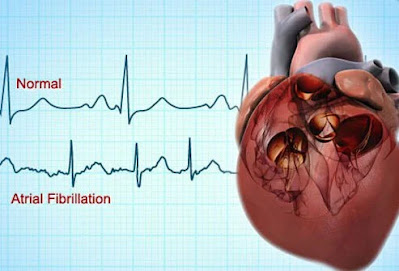

Ακανόνιστος καρδιακός παλμός (αρρυθμία)

Οι αρρυθμίες είναι ένας άλλος τύπος καρδιακής νόσου που μπορεί να αυξήσει τον κίνδυνο εμφράγματος ή εγκεφαλικού.

Οι ασθενείς που παρατηρούν ότι οι καρδιακοί τους παλμοί είναι ασυνήθιστα γρήγοροι, βραδείς ή ακανόνιστοι μπορεί να βιώνουν ακανόνιστους ηλεκτρικούς παλμούς που ονομάζονται αρρυθμίες. Μπορεί επίσης να έχουν συμπτώματα αδυναμίας, δύσπνοια και άγχος. Οι αρρυθμίες μπορούν να αλλάξουν, να επιβραδύνουν ή ακόμα και να σταματήσουν την ικανότητα της καρδιάς να αντλεί αίμα.

Κατά συνέπεια, τα άτομα με αρρυθμίες πρέπει να αναζητήσουν επείγουσα ιατρική φροντίδα, ειδικά εάν η αρρυθμία είναι επίμονη ή προκαλεί συμπτώματα που σχετίζονται με συμπτώματα καρδιακής προσβολής, όπως πόνος στο στήθος. Η κοιλιακή μαρμαρυγή και η κολπική μαρμαρυγή είναι δύο παραδείγματα αρρυθμιών. Η κολπική μαρμαρυγή μπορεί να αυξήσει τον κίνδυνο εγκεφαλικού επεισοδίου.

Έλεγχος καρδιακών παθήσεων: ΗΚΓ (Ηλεκτροκαρδιογράφημα)

Ένα ΗΚΓ μετρά την ηλεκτρική δραστηριότητα του καρδιακού παλμού.

Η ηλεκτρική δραστηριότητα της καρδιάς μπορεί να φανεί με ηλεκτροκαρδιογράφημα.

Τα ΗΚΓ είναι εξετάσεις που παρέχουν σημαντικές πληροφορίες στον ιατρό για τον καρδιακό ρυθμό, τη βλάβη στην καρδιά ή την καρδιακή προσβολή και μπορεί να παρέχουν πολλές άλλες σημαντικές πληροφορίες ή ενδείξεις για την κατάσταση του ασθενούς. Επιπλέον, τα ΗΚΓ μπορούν να συγκριθούν με προηγούμενα και μελλοντικά ΗΚΓ για να φανούν οι αλλαγές στην ηλεκτρική δραστηριότητα της καρδιάς με την πάροδο του χρόνου ή μετά από θεραπείες.